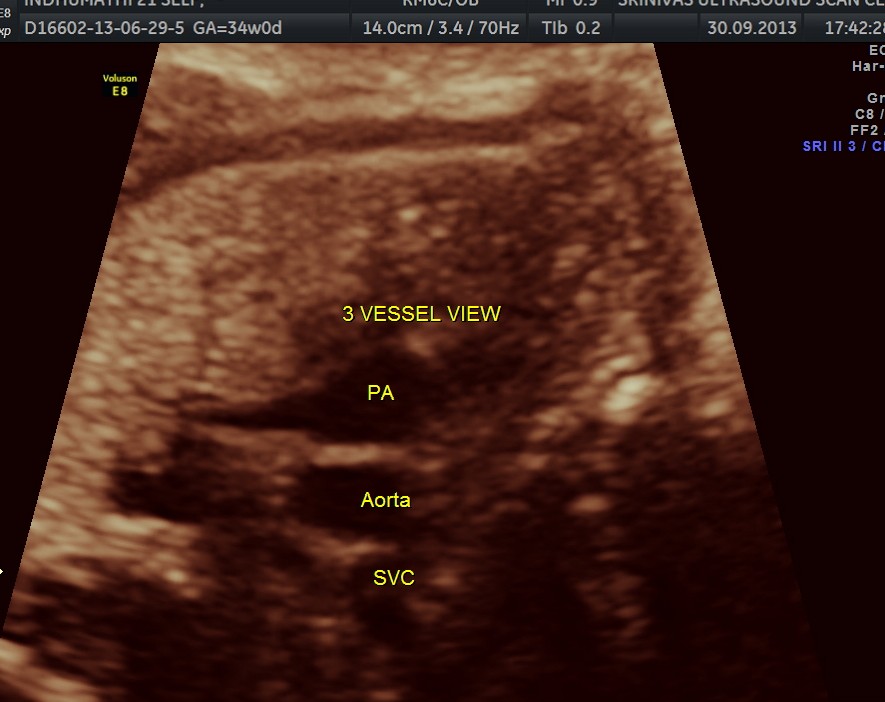

The following are of the 34 weeks gestation :

The 4 chamber view shows the patent foramen ovale. 2 pulmonary veins are also seen entering the left atrium.